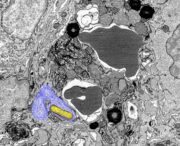

Kolonkarzinom: Forschende identifizieren Schlüsselgene für deren Entwicklung

Obwohl manche der mit Darmkrebs assoziierten molekularen Veränderungen bekannt sind, ist ihr Beitrag zur Krebsentstehung noch nicht genau geklärt.